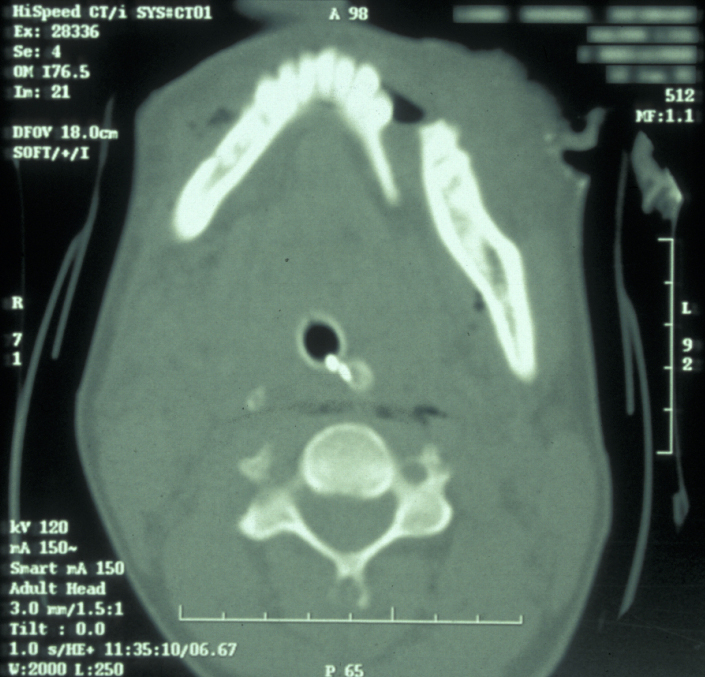

If the patient is unable to stand in the DPT machine, left and right lateral oblique mandibular views will give good imaging of the body of the mandible.  If the patient has multiple complex maxillofacial fractures a CT scan (CT coronal and axial images, with or without 3D reformatting) is helpful (see Figure 4). The CT scan will help assess condylar fracture position, angulation and any fractured dislocation of the condylar head. A CT scan is also useful to image multi-part mandibular body fractures.

Figure 4: CT scan of a displaced mandibular fracture.

Figure 5: CT scan of bilateral condylar fractures; note the overlap of fragments.